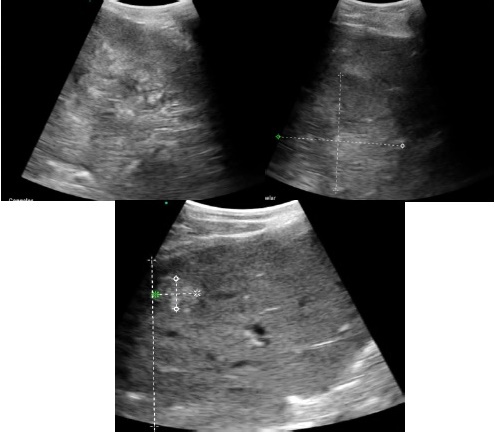

Se realiza ultrasonido abdominal evidenciando múltiples lesiones hepáticas (Figura 1).

Figura 1 Ultrasonido abdominal en el que se observa hígado de patrón heterogéneo a expensas de lesiones de aspecto hiperecogenico a predominio central, sin alteracion del detalle vascular, porta o vias biliares.